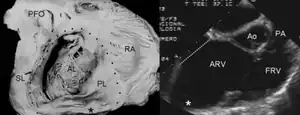

Ebstein's anomaly shows dilatation at atrioventricular junction and aneurysmal fibrous sac asterisk (and echocardiogram asterisk) -